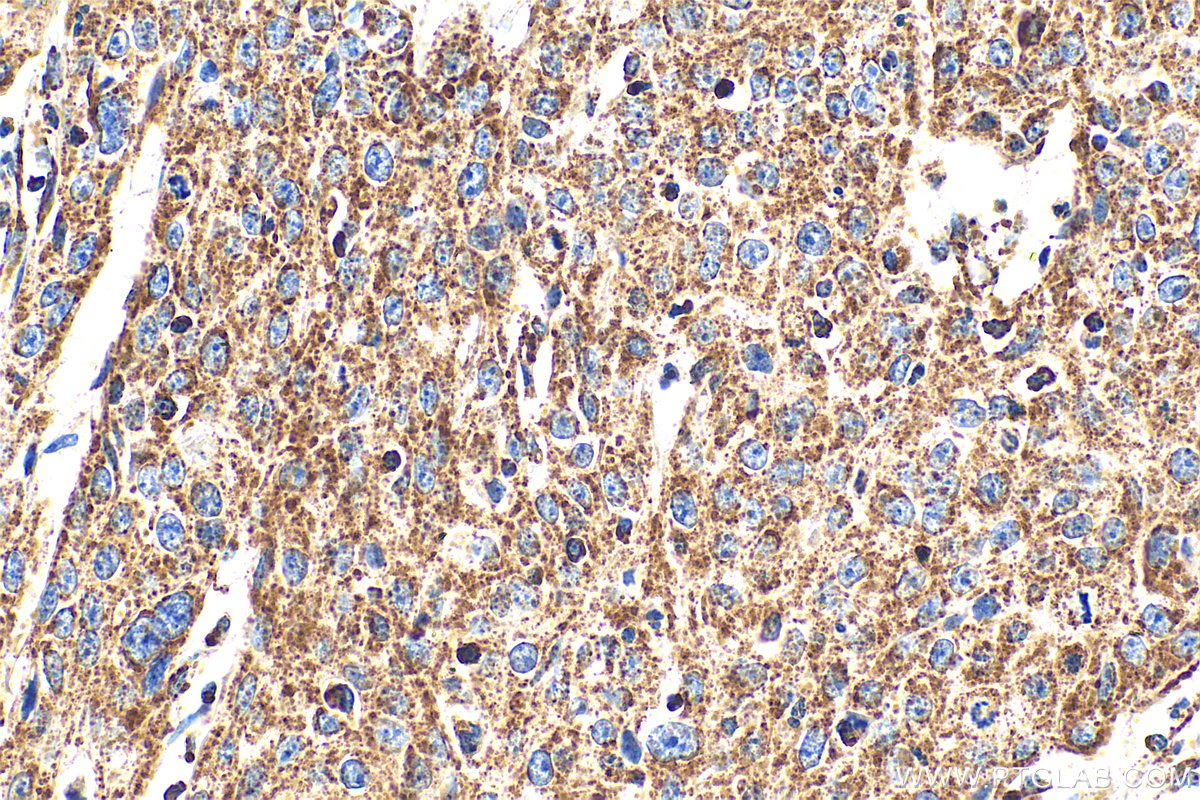

| Positive IHC detected in | human cervical cancer tissue, human breast cancer tissue Note: suggested antigen retrieval with TE buffer pH 9.0; (*) Alternatively, antigen retrieval may be performed with citrate buffer pH 6.0 |

| Immunohistochemistry (IHC) | IHC : 1:50-1:500 |